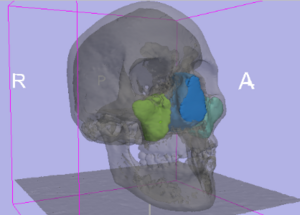

Publication: PLoS One. 2016 Jan 11;11(1):e0145987. PMID: 26751685 | PDF Authors: Zhan Q, Chen X. Institution: School of Mechanical Engineering, Shanghai Jiao Tong University, Shanghai, China. Background/Purpose: This paper proposes an interactive method of model clipping for computer-assisted surgical planning. The model is separated by a data filter that is defined by the implicit function of the clipping path. Being interactive to surgeons, the clipping path that is composed of the plane widgets can be manually repositioned along the desirable presurgical path, which means that surgeons can produce any accurate shape of the clipped model. The implicit function is acquired through a recursive algorithm based on the Boolean combinations (including Boolean union and Boolean intersection) of a series of plane widgets' implicit functions. The algorithm is evaluated as highly efficient because the best time performance of the algorithm is linear, which applies to most of the cases in the computer-assisted surgical planning. Based on the above stated algorithm, a user-friendly module named SmartModelClip is developed on the basis of Slicer platform and VTK. A number of arbitrary clipping paths have been tested. Experimental results of presurgical planning for three types of Le Fort fractures and for tumor removal demonstrate the high reliability and efficiency of our recursive algorithm and robustness of the module. Funding:

A snapshot of the module SmartModelClip in 3D Slicer. On the left is the operator command view that users can create and manipulate clipping path and thickness plane(i.e., they can create, hide and delete plane widgets). Users can also reverse the directions of the axes of the both clipping path and thickness plane widget. On the right is the scene that users can interact with the clipping path. They can specify the fiducial points that position the clipping path and modify the boundary of the clipping path by dragging the handles to obtain the desirable clipping path. |